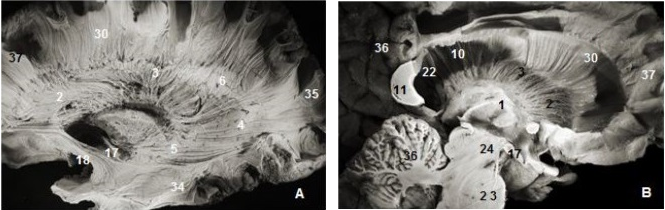

Figure 4.(A) Lateral view of left cerebral hemisphere after dissection and (B) coronal view. 2. Anterior thalamic radiation, 7. Subependymal stratum, 8. Corpus callosum, 12. Internal capsule, 13. External capsule, 13. SLF, 15. Corona radiata, 16. Uncinate fasciculus, 19. Inferior frontal occipital fasciculus, 27. Putamen, 28. Globus pallidus, 29. lateral ventricle, 31. Parietal pole, 34. Temporal pole.

Our dissections failed to identify the occipitofrontal fasciculus connecting the frontal and occipital lobes which was different from the sub-ependymal stratum and anterior and superior thalamic radiations. The following is our stepwise dissection as anatomic structures are exposed in the order they appear. The removal of the external capsule and claustrum exposed the lateral surface of the putamen.

The internal capsule was exposed after the excision of the putamen and globus pallidus which were perfectly identifiable. The abscission of the outermost fibers of the internal capsule situated approximately 26 mm from the cerebral cortex and the head of the caudate nucleus exposed thalamic radiations (Figure 3).

The C-shaped uncinate fasciculus (UF) connects the frontal and temporal lobes. The uncinate fasciculus (Figure 2, Figure 4) is composed of 3 parts: a fanning frontal end, an insular segment where the fibers are grouped together and a polar temporal extremity. The insular segment was discovered after the removal of the insular cortex laterally, the extreme capsule medially which consists of arcuate fibers connecting the insula to the opercula except the portion near the falciform fold. The last plane was exposed after the ablation of the claustrum and the extreme capsule which are below the tip of the insular cortex which is lateral to the limen insulae and medial to the claustrum. At this level, the posterior and superior margins were closely attached th lower edge of the inferior occipito frontal bundle. The detachment and excision of this fasciculus exposed the frontal and temporal rapports of the uncinate fasciculus.

The frontal end was discovered after complete removal of the orbital part of the lower frontal gyrus, the pars orbitalis of the upper frontal gyrus and the subcallosal area. The anterior and inferior surfaces were part of the internal capsule. Its anterior margin sweeps from below upward from the isthmus, the lateral edge of the anterior perforated substance and the junction between the lateral and inferior surfaces of the head of the caudate nucleus respectively. Its posterior edge was attached along its full length to the anterior border of the inferior occipitofrontal fasciculus (IOFF). The medial surface of the upper frontal end covered the anterior edge of the putamen and the inferior surface of the head of the caudate nucleus.

The temporal end is distributed to the uncus, the amygdala and the temporal gyri. Here too, the detachment and excision of the IOFF helped the study of the temporal distributions of the uncinate fasciculus. The insular segment was 2mm thick and 8.8mm wide.

The inferior occipitofrontal fasciculus (Figure 2, Figure 4) closely attached to the previous fasciculus was composed of fiber bundles connecting the frontal lobe to the temporal, posterior parietal and occipital lobes. The IOFF is shaped somewhat like a flattened tape and is composed, as the uncinate fasciculus, of three parts: frontal, insular and parietal temporo-occipital segments.

The insular segment was fully exposed after the ablation of the uncinated bundle and courses medial to the external and extreme capsule and above the uncinate fasciculus. This segment was on average 2 mm thick and 8.8 mm wide.

The parietal temporo-occipital segment is about 20 mm wide stretching from the amygdala to the pulvinar and geniculate bodies at the height of the ventricular atrium.

The fanning frontal segment is located at the height of the frontal horn of the lateral ventricle. The frontal distribution of the inferior occipitofrontal fasciculus stretches to the whole of Broca's area. This frontal end was located 25 mm away from the cortex of the lower frontal gyrus. It is the second fasciculus connecting the frontal and the occipital lobes, and is thin at the frontal end.

The sub-ependymal stratum also known as the subcallosal stratum was made of a fiber-free layer of white matter. This layer of white matter was exposed after excision of the ependymal layer lining the ventricular system. It is located between the caudate nucleus and callosal radiations (Figure 1, Figure 2, Figure 4). Under the ependyma backward to the occipital horns, callosal fibers form together the tapetum and thalamic radiations. Our dissection failed to show a precise boundary between the tapetum and the sub-ependymal stratum. The substratum is a sub-ependymal structure located between the caudate nucleus, the corpus callosum radiations and the internal capsule. Globally, it is located below the ependyma and medial to the cingulum. It is not made of fibers connecting the frontal and the occipital lobes.